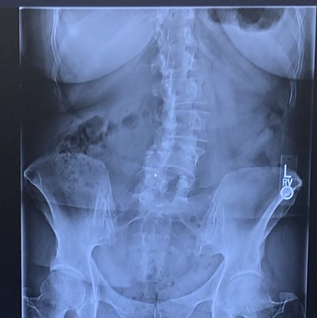

Richard Markx

My right hip pain had been getting worse and worse, and I finally had an x-ray taken in CA by a local orthopedist who told me I definitely needed a total hip replacement. Having lived in NY most of my life I knew I wanted to have the surgery at HSS. I called an old acquaintance, a shoulder specialist, for a referral. I had not spoken to him in 20 years and left a message with his office staff. He called me back and without any hesitation told me the only doctor he would recommend was Dr. Jose Rodriguez! I immediately called his office and his practice manager Evelyn was Superwoman, getting me in for pre-op visits and the surgery in 3 weeks. By the time my wife and I flew to NY for the surgery I needed a wheelchair to get through airports, up to the hotel and to HSS the morning of the surgery. As soon as I woke up in recovery I knew the surgery went well. NO MORE PAIN!! It is now 7 weeks post-op and I feel like a new person!! My heartfelt thanks to Dr. Rodriguez, his staff and all the HSS employees who I was fortunate to have come in contact with. Many many thanks!